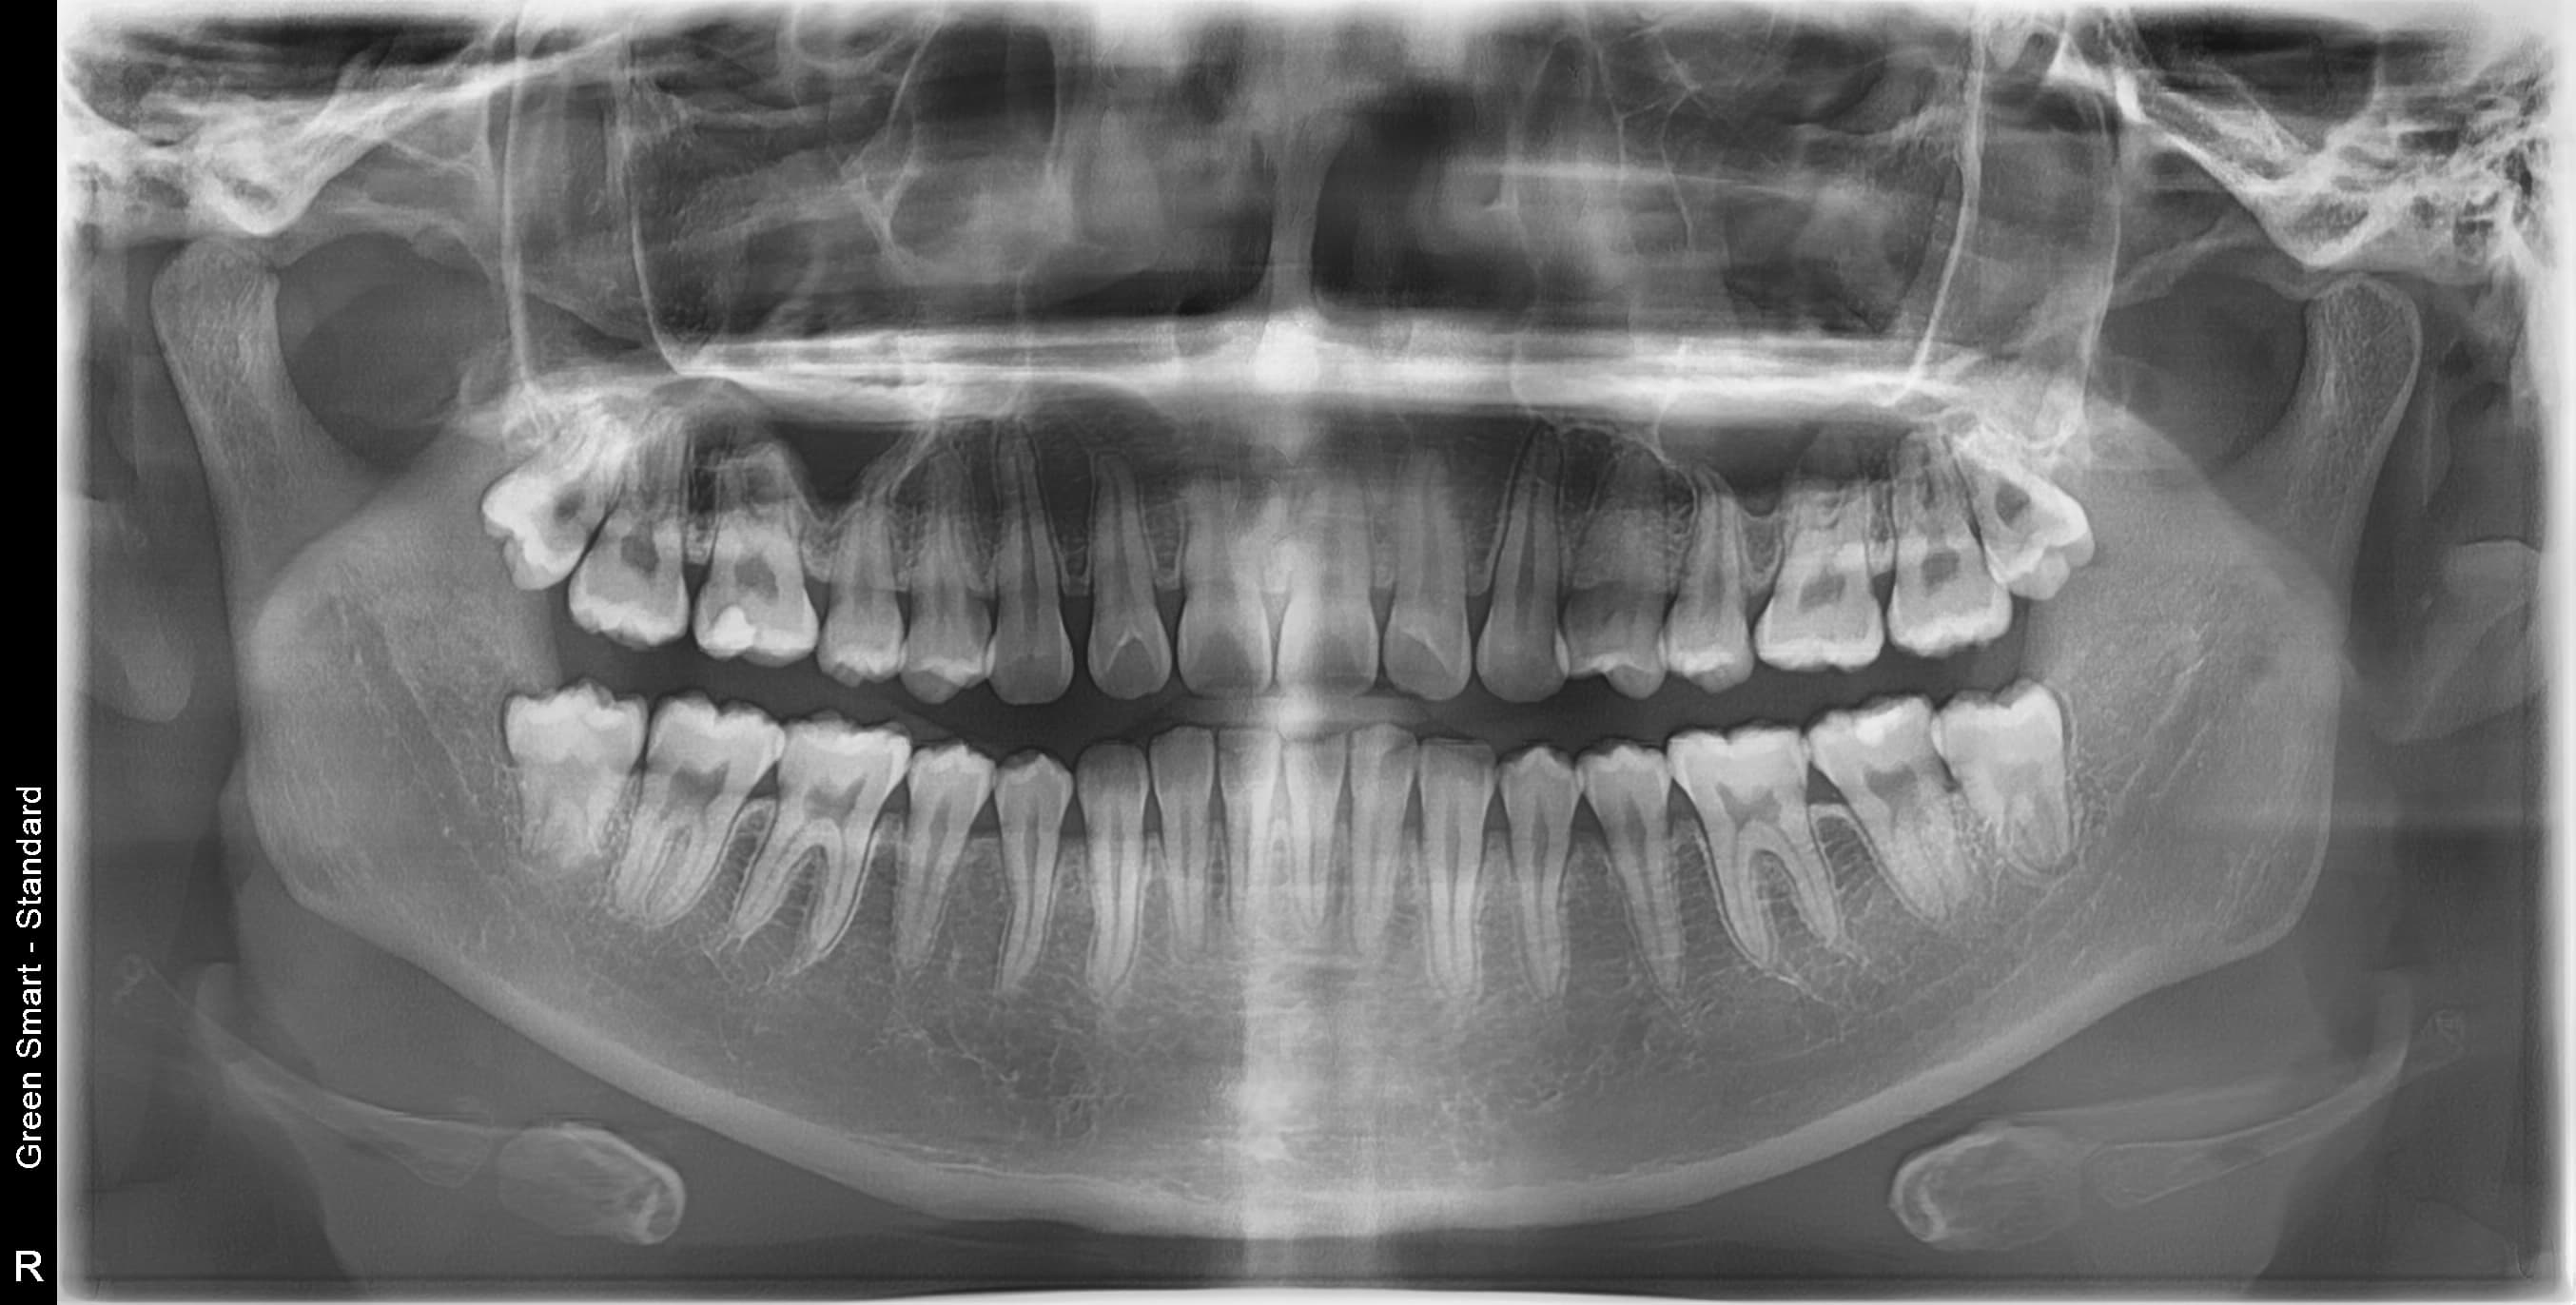

누운 사랑니

옆으로 누워 자라며 옆 치아를 압박할 수 있습니다

사랑니 상태별 위험도

저위험

정상 사랑니

정상적으로 자란 사랑니도 관리가 어려워 충치 위험이 높습니다

중위험

부분매복 사랑니

음식물이 끼기 쉽고 염증이 자주 발생합니다

고위험

완전매복 사랑니

낭종 형성 가능성이 있어 조기 발치가 필요합니다

치근만곡 사랑니

뿌리가 구부러져 있어 발치 난이도가 높습니다

즉시 처치 필요

수평매복 사랑니

앞 치아를 밀어 치열 불균형과 충치를 유발합니다